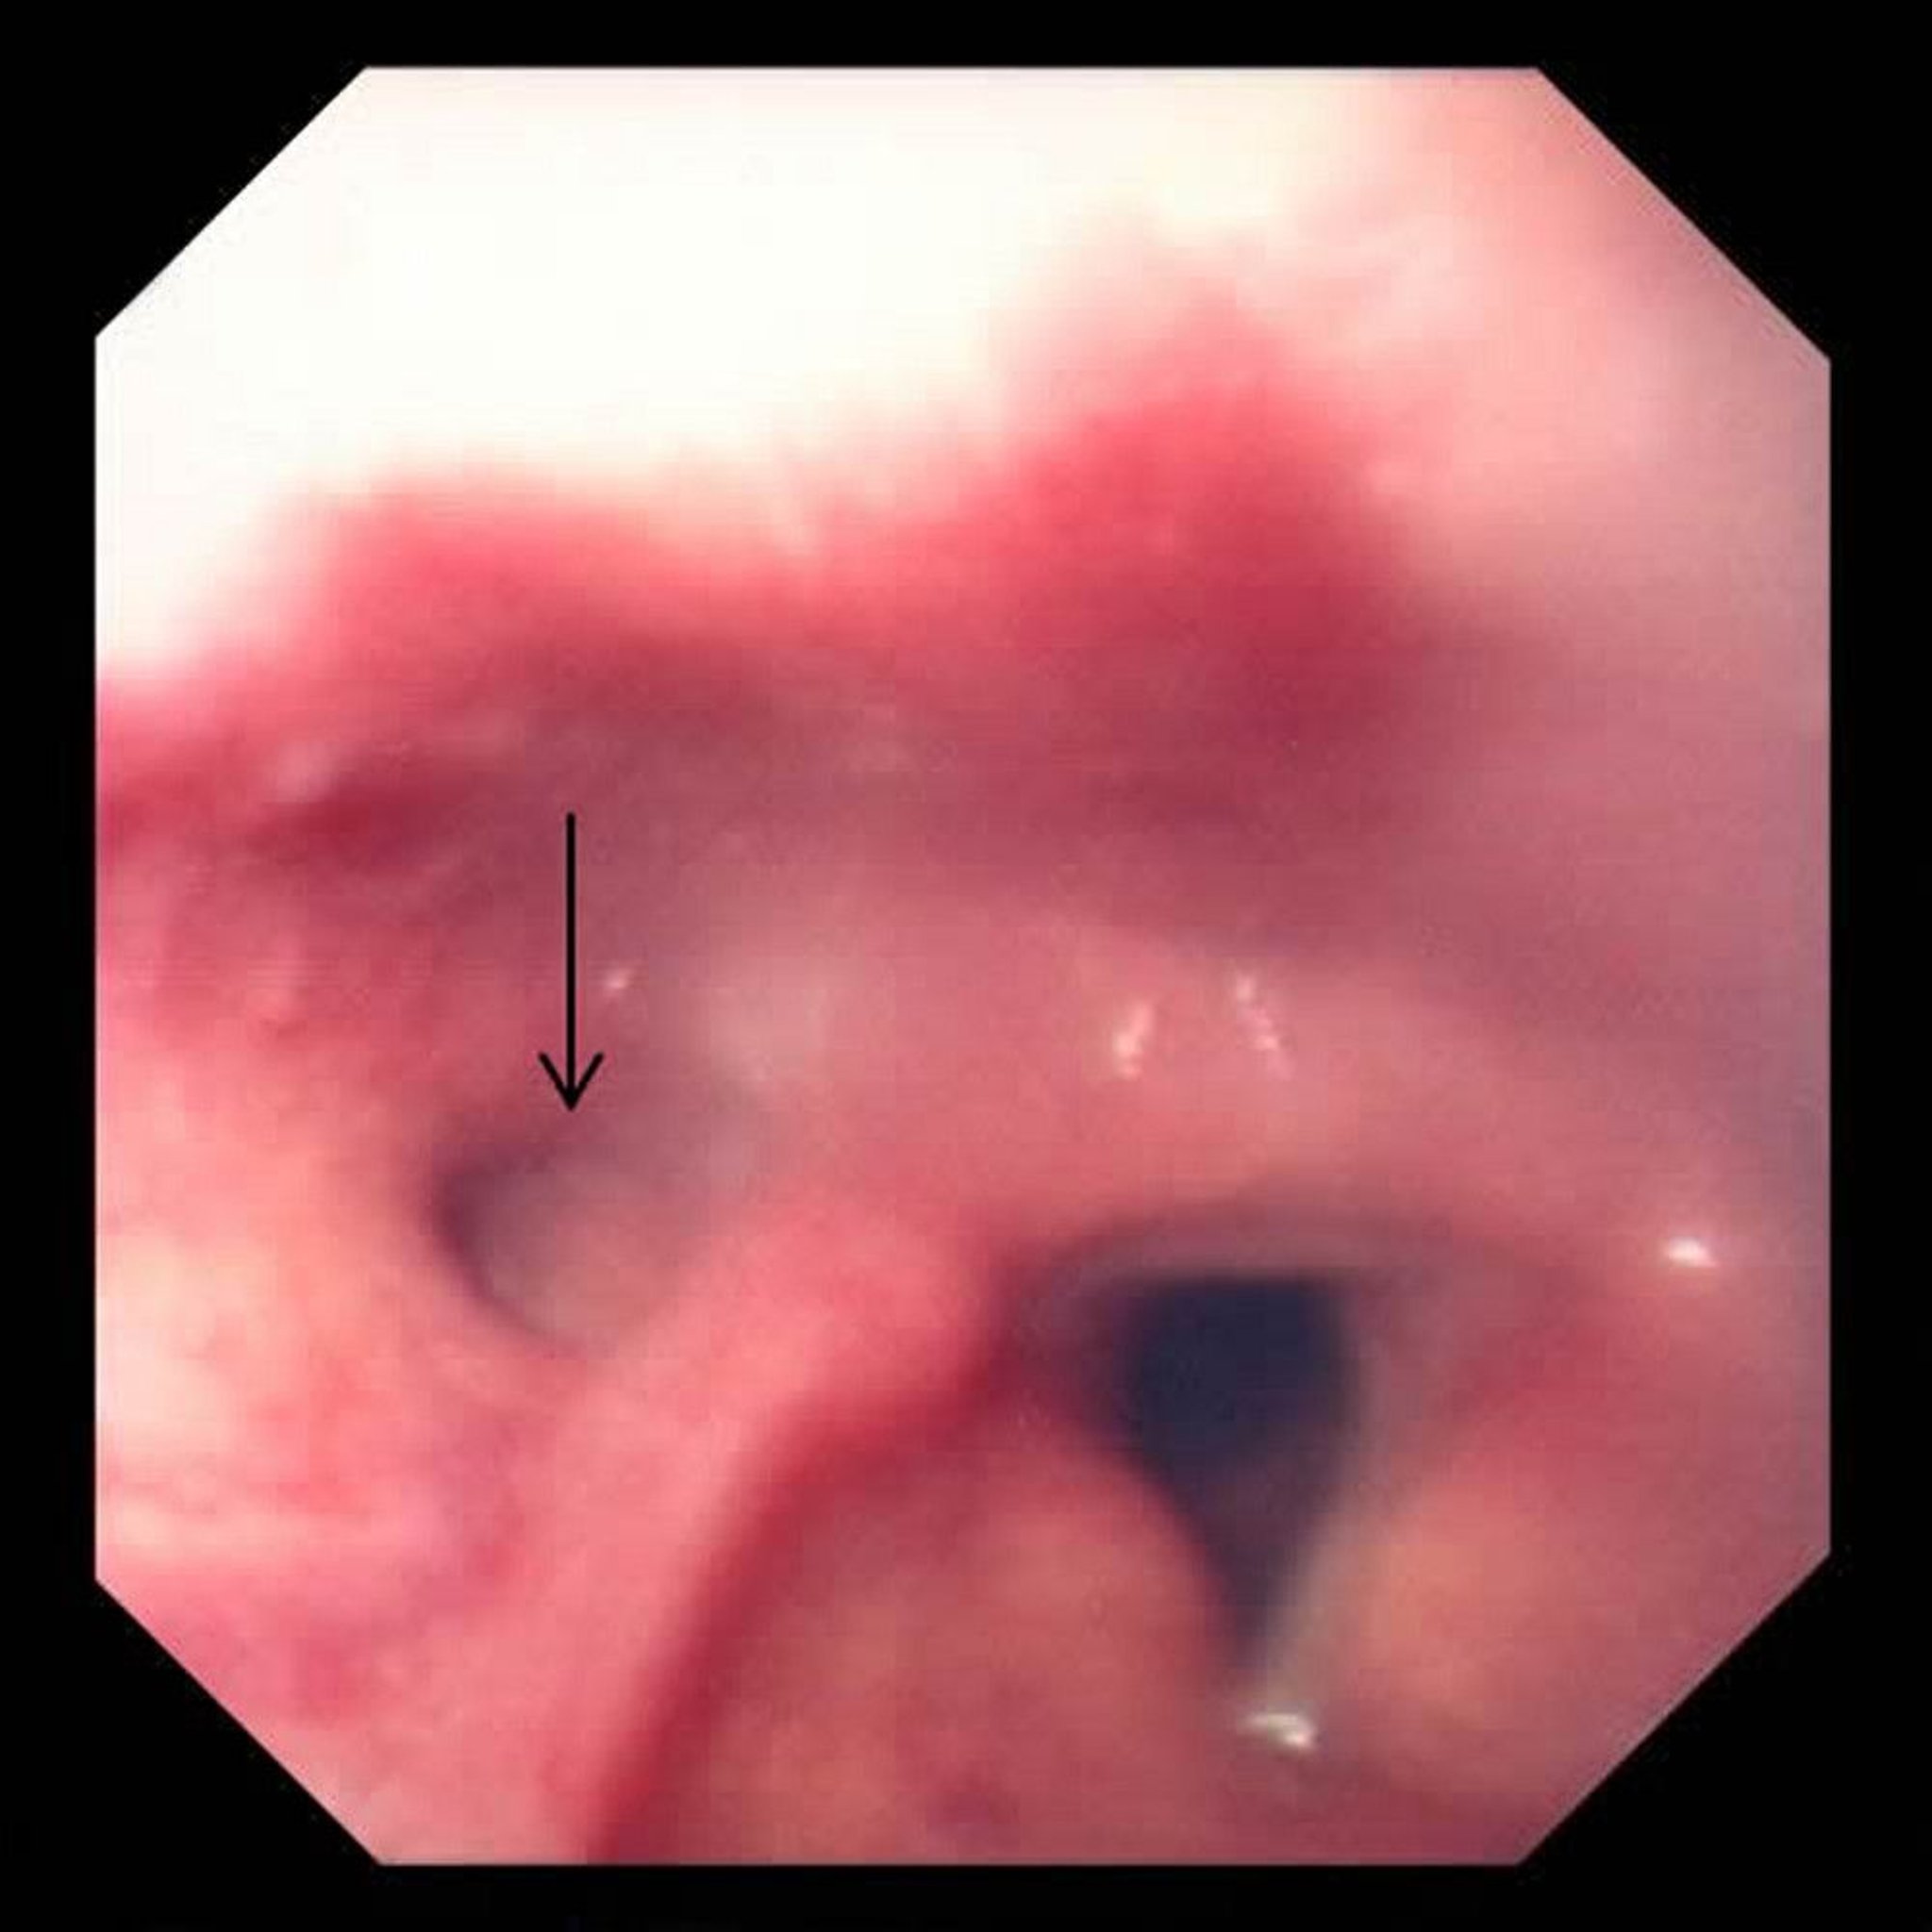

In this photo, the diverticulum is on the left (arrow), next to the triangular opening of the windpipe (trachea, right) formed by the vocal cords.

Photo provided by David M. Martin, MD.